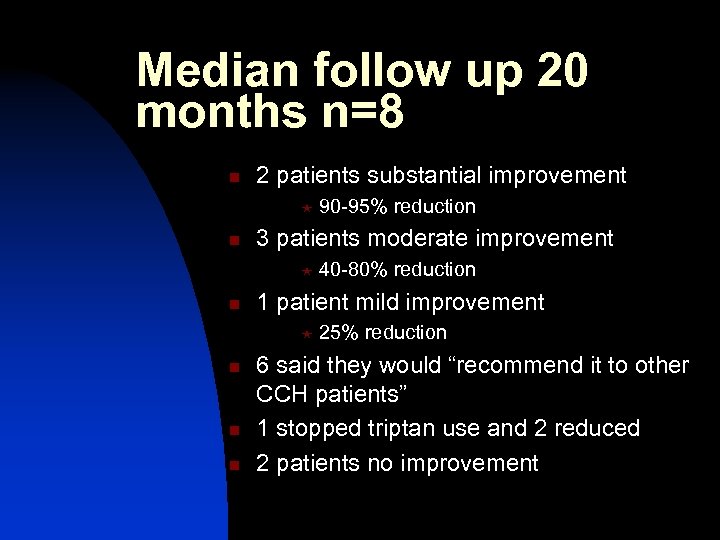

Median follow up 20 months n=8 n 2 patients substantial improvement « n 3 patients moderate improvement « n n n 40 -80% reduction 1 patient mild improvement « n 90 -95% reduction 25% reduction 6 said they would “recommend it to other CCH patients” 1 stopped triptan use and 2 reduced 2 patients no improvement